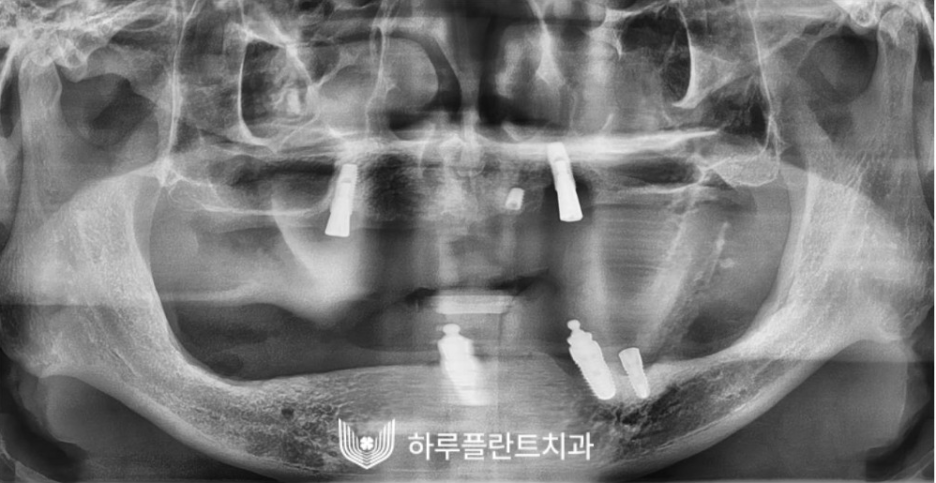

수술 성공 케이스 1

2021.04

이 분은 상악동이 너무 크고

하치조 신경과의 거리가 너무 가까워서

타치과에서 임플란트 불가 판정을 받고

하루플란트치과에 내원하신 분입니다.

하치조 신경은 아래턱 신경에서 일어나

턱뼈관으로 들어가 아래 치아와

아래턱뼈에 분포하는 신경으로

하치조 신경과의 거리가 너무 가까운 경우

뼈이식을 통해서 잇몸뼈를 확보해준다면

하치조 신경과의 거리가 확보되어

임플란트를 식립할 수 있는 공간이 생깁니다.